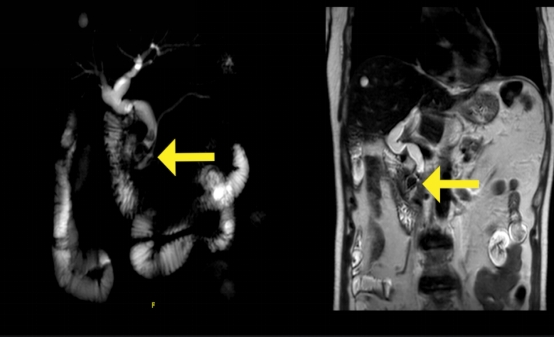

入院七天前,老杨晚饭后感到腹胀,紧接着出现恶心呕吐,全身皮肤发黄,尿色加深,于是来到ac米兰官网中文网站一院就诊。经过初步检查,老杨的主要病症确定是在胆总管有几颗鹌鹑蛋大小的结石阻塞整个胆道系统的最终通道,同时CT检查还发现胃也长了肿瘤。

在麻醉科、手术室的通力配合下,手术顺利进行。术中,孟宪志在荧光技术的辅助下,经过细致解剖,顺利找到已经完全脱离原来解剖位置的胆总管,患者胆总管结石被顺利取出,同时将胃部肿瘤也一并切除,经腹壁1cm的小切口取出。术后7天,患者康复出院。

孟宪志介绍,荧光腹腔镜技术是一项新型的手术技术。术前,在患者的血液里注入荧光剂,荧光剂随着血液进入肝脏代谢然后进入胆囊、胆总管等肝内外胆道系统。术中,应用特殊的荧光镜头充当医生的眼睛,就能看见闪闪发光的充满荧光剂的胆管,为医生的手术操作提供导航。术后,荧光剂从患者的消化系统或泌尿系统排出体外,无任何毒副作用。